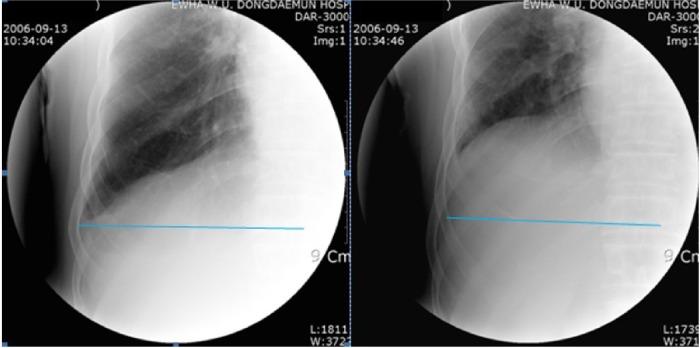

Among 117 patients with COPD receiving pulmonary rehabilitation who underwent the initial fluoroscopy-guided chest X-ray and pulmonary function test, 37 of those patients who underwent both initial and follow-up fluoroscopy and pulmonary function tests were enrolled in this study. After hospital education, participants received pulmonary rehabilitation through regular home-based training for at least 3 months by the same physiatrist. We assessed the changes in diaphragm area with fluoroscopy-guided posteroanterior chest X-rays between pre- and postpulmonary rehabilitation. To minimize radiation hazards for subjects, the exposure time for fluoroscopy to take chest X-rays was limited to less than 5 seconds.

There were significant improvements (2,022.8±1,548.3 mm(2) to 3,010.7±1,495.6 mm(2) and 2,382.4±1,475.9 mm(2) to 3,315.9±1,883.5 mm(2); right side P=0.001 and left side P=0.019, respectively) in diaphragmatic motion area during full inspiration and expiration in both lungs after pulmonary rehabilitation. Pulmonary function tests showed no statistically significant difference between pre- and postpulmonary rehabilitation.

The study suggests that the strategy to assess diaphragm movement using fluoroscopy is a relatively effective tool for the evaluation of pulmonary rehabilitation in COPD patients in terms of cost and time savings compared with computed tomography or magnetic resonance imaging.

在117例接受肺康复的COPD患者中,这些患者均接受了初始荧光透视引导的胸部X线检查和肺功能测试,其中37例同时接受了初始和随访荧光透视及肺功能测试的患者被纳入本研究。经过医院教育后,参与者由同一位物理治疗师通过定期的家庭训练接受至少3个月的肺康复。我们通过荧光透视引导的前后位胸部X线检查评估肺康复前后膈肌面积的变化。为了将受试者的辐射危害降至最低,荧光透视拍摄胸部X线的曝光时间限制在5秒以内。

肺康复后,双肺在完全吸气和呼气时的膈肌运动面积均有显著改善(右侧从2,022.8±1,548.3平方毫米改善至3,010.7±1,495.6平方毫米,左侧从2,382.4±1,475.9平方毫米改善至3,315.9±1,883.5平方毫米;右侧P = 0.001,左侧P = 0.019)。肺功能测试显示肺康复前后无统计学显著差异。

该研究表明,与计算机断层扫描或磁共振成像相比,使用荧光透视评估膈肌运动的策略在评估COPD患者的肺康复方面是一种相对有效的工具,在成本和时间节省方面具有优势。